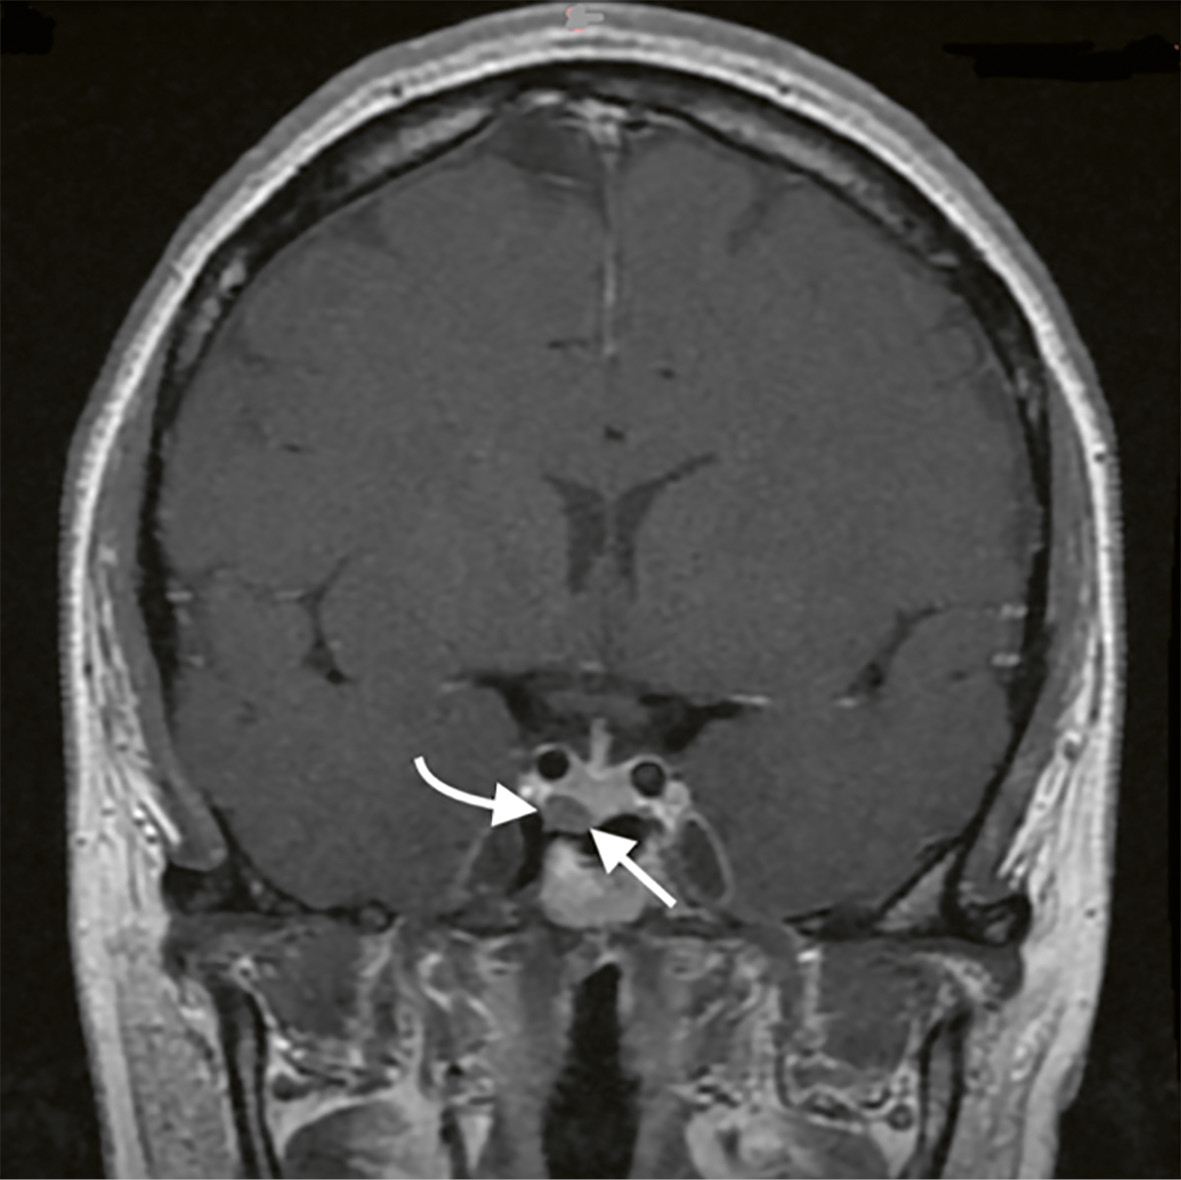

По данным повторного МРТ головного мозга с контрастным усилением, визуализирована эндо-инфраселлярная микроаденома гипофиза размерами 7,5x6x8,8 мм (рис. 1).

Рисунок 1. МРТ головного мозга с внутривенным болюсным контрастированием.

Примечание: на фронтальных снимках в режиме Т1 с контрастным усилением визуализируется эндо-инфраселлярная аденома гипофиза (белые стрелки).